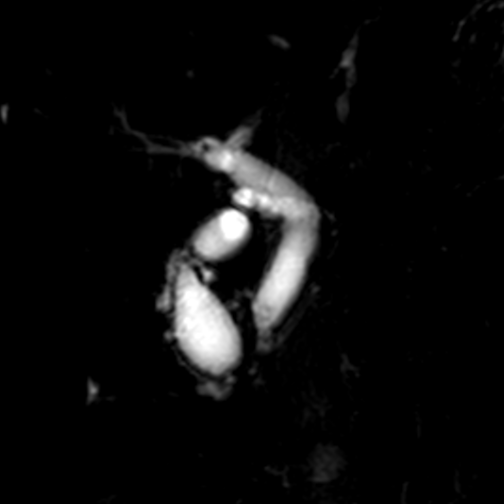

图片

▲患者MRCP(胰胆管水成像)